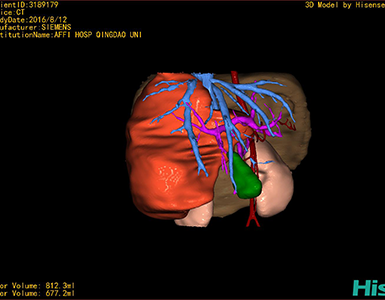

将0.625mm双源薄层CT资料的静脉期和动脉期Dicom格式文件导入海信CAS系统。

通过调节窗宽窗位调整CT序号,对肿瘤,肝实质,胆囊,下腔静脉,肿瘤,肝动脉、门静脉及肝静脉等进行三维重建;系统自动计算肿瘤体积和肝脏体积。

模拟手术操作,自动计算切除肿瘤体积。肝脏体积为660.9ml,肿瘤体积为812.3ml,肿瘤体积为肝脏体积的122.9%,通过比对3-4岁正常肝脏体积为522.63±121.24 ml,肿瘤所占比例较大,且包裹右侧肾脏、及腹腔大血管,手术无法完整切除肿物,不建议给予手术治疗。